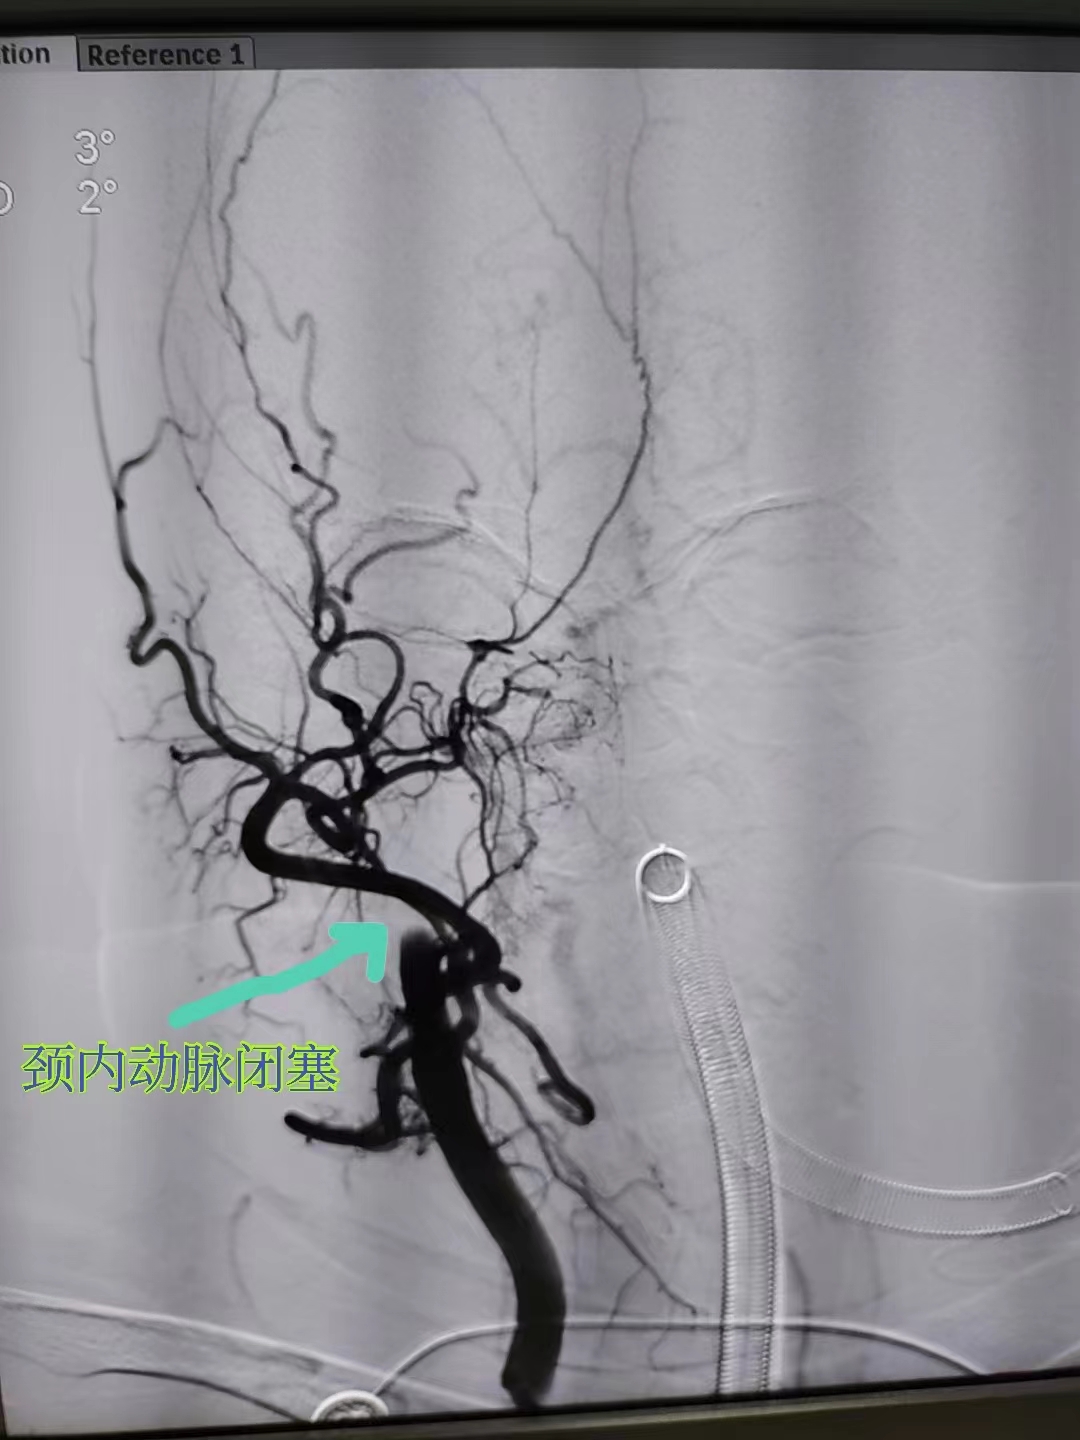

造影发现郑阿姨右侧颈内起始部闭塞

取栓治疗主要是针对颅内大血管闭塞。通过导管经血管内到达闭塞部位,使用特殊的取栓装置将血栓取出,恢复闭塞部位血流。

时间就是大脑!0:09,神经内科团队为郑阿姨给予阿替普酶静脉溶栓,之后立即将其送至导管室进行介入取栓,30分钟后成功将血栓取出,45分钟成功将狭窄的颈动脉扩张成形实现血管再通。